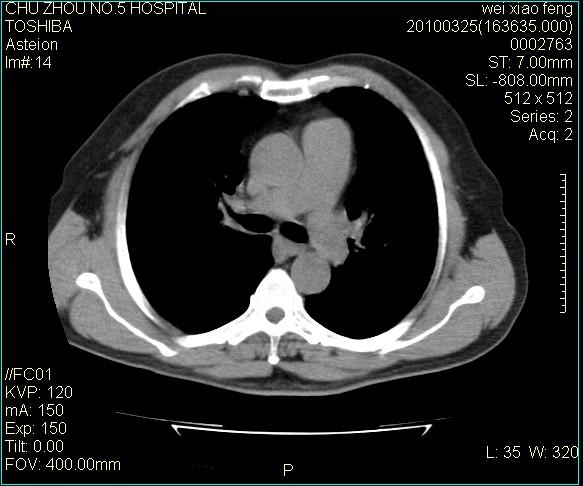

男,60岁,反复咳、痰、喘3月,加重3天。

间质性肺炎伴间质纤维化!不排除伴有职业病!

考虑间质性肺炎伴间质纤维化。

间质病变,间质炎症,间质纤维化趋势

右肺中叶结节影为原发灶,考虑右肺中叶周围型肺癌并淋巴道转移